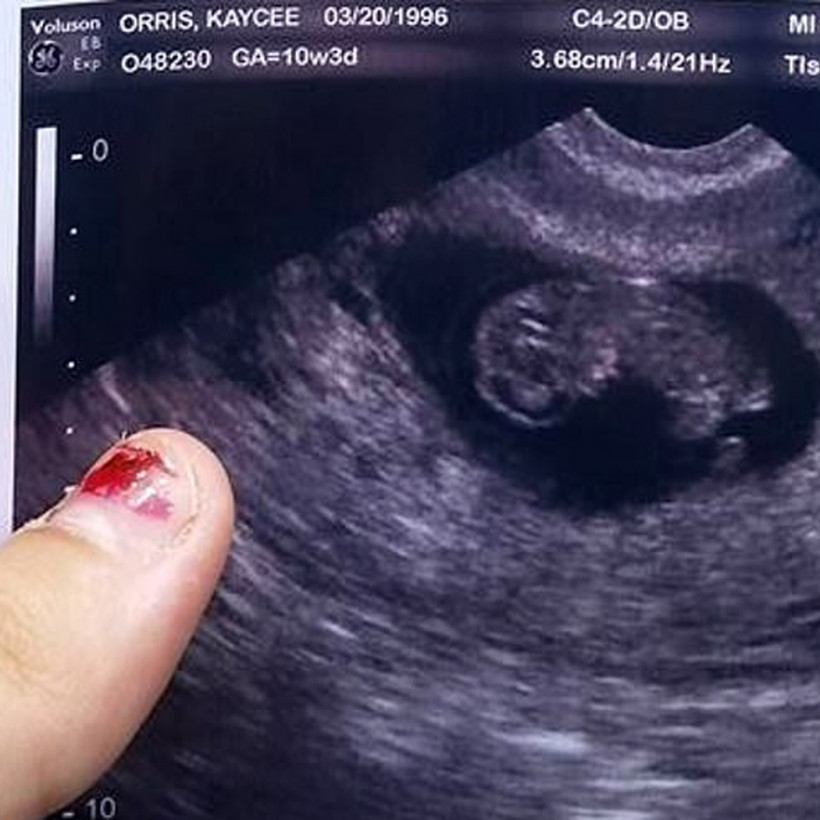

Η Kaycee και ο Geoffrey από την Pennsylvania σκέφτηκαν το «απόλυτο σχέδιο». Το ζευγάρι σκηνοθέτησε τη γέννηση και τον θάνατο του... ανύπαρκτου μωρού τους.

Επί εννιά ολόκληρους μήνες οι δύο νέοι προσποιούνταν ότι περίμεναν παιδί. Αυτό νόμιζαν τουλάχιστον συγγενείς και φίλοι.

Στις 3 Ιουλίου η Kaycee και ο Geoffrey ανακοίνωσαν ότι «έφεραν στον κόσμο» τον γιο τους, όμως πέθανε πέντε ώρες μετά τη γέννησή του. Το ζευγάρι άνοιξε και λογαριασμό στο GoFundMe, ώστε να συγκεντρώσουν χρήματα για την κηδεία του αδικοχαμένου βρέφους.

Σύμφωνα με τις Αρχές, στη φωτογραφία που έχουν αναρτήσει στο Facebook, το μωρό τους είναι απλά... μια κούκλα.

Δείτε στην gallery πώς είχαν στήσει το σχέδιο τους: